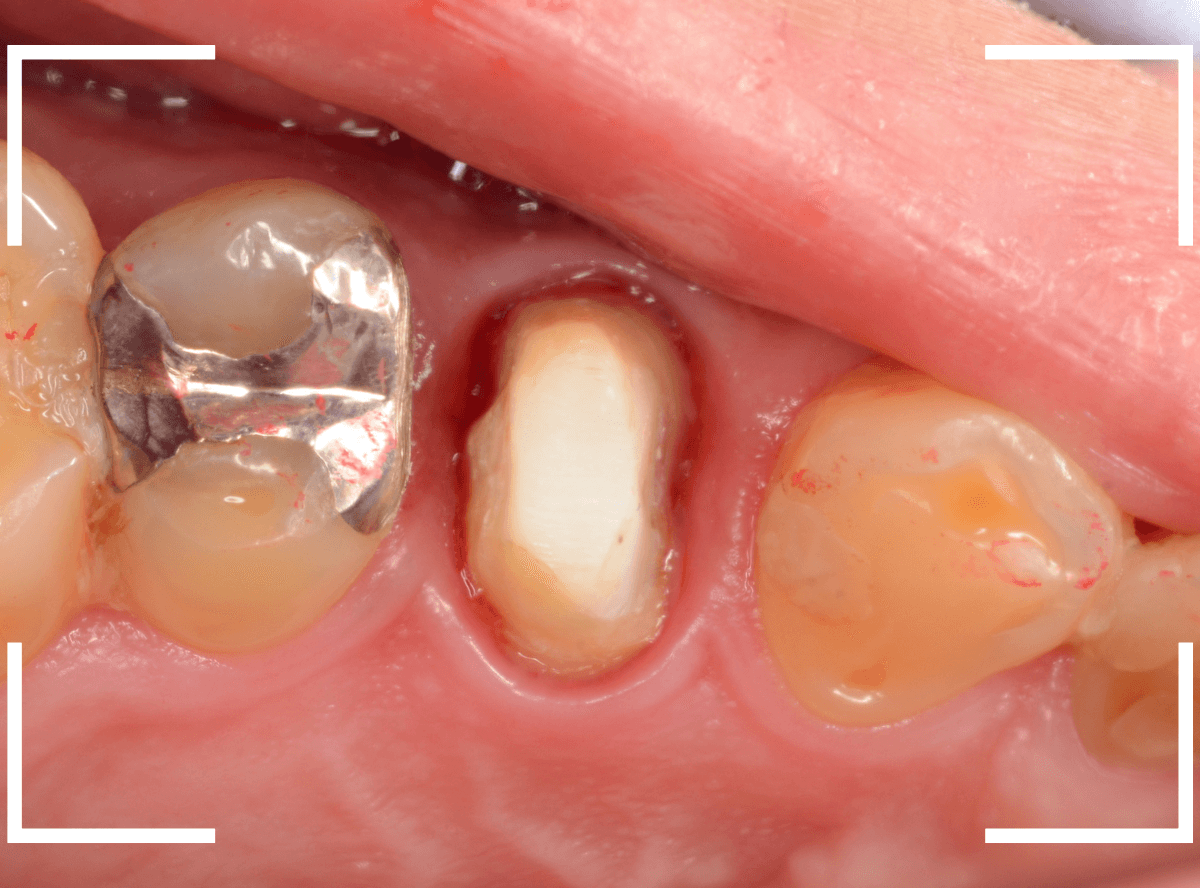

Case.10

さし歯を入れるスペースがない!

一番奥の歯が土台(コア)の治療までで中断してしまってる患者さんの例です。

本来であれば、この上にさし歯を作らなければいけないのですが、この時点でかみ合ってしまい、さし歯を作ろうにも作りづらい状況でうやむやのうちに治療中断になってしまったようです。

まず、土台の治療をしてから時間が経過していることと、不適合になっている事から、外して中を調べます。

すると、土台の中で虫歯にもなっていました。

(〇部の赤い部分)

こういった事は、レントゲン写真でもよくわからない事が多く、土台を外す治療は本当に神経を使います。

今回は、歯肉の中まで歯が欠損しているので、このまま土台とさし歯を作り直しても、いい結果にはなりません。

患者さんに状況を説明し、歯の周りの歯肉を麻酔をして電気メスでトリミングします。

このように歯の際が歯肉からしっかり出てる状況で製作しないと、さし歯はしっかりお口の中で安定しません。

この状態で新しい土台(ファイバー・コア)の型を取ります。